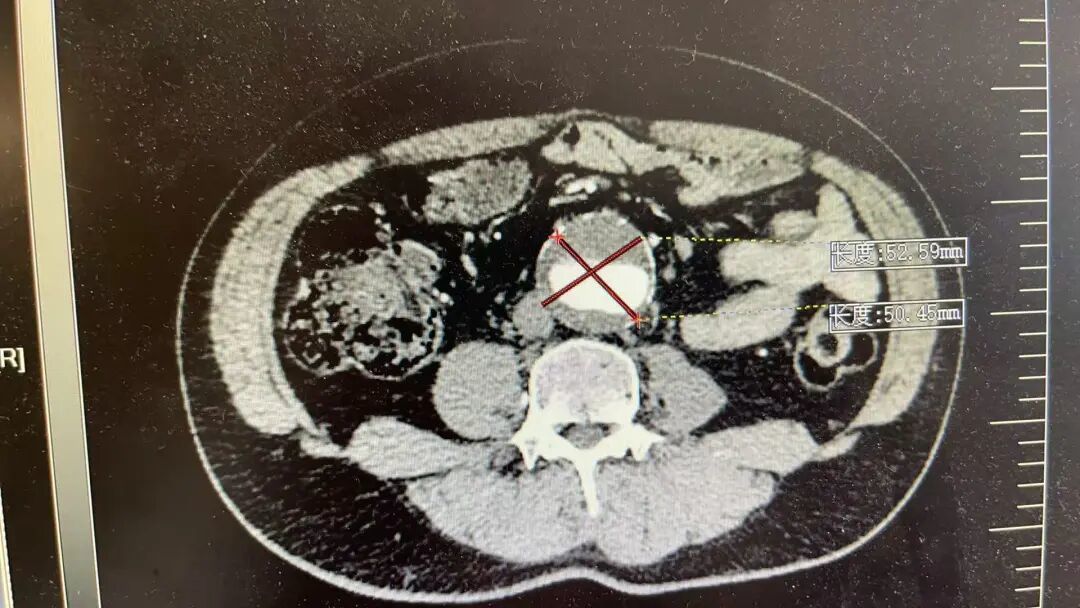

这两位患者情况差不多,他们平日里身体并无明显不适,在一次常规体检中,腹部超声检查结果显示,腹主动脉存在瘤样扩张,进一步检查确诊为腹主动脉瘤,并同时累及双侧髂总动脉,形成髂动脉瘤。

腹主动脉是人体腹部最粗大的一根动脉,大致位于肚脐的后面、脊柱的前面,负责将心脏泵出的血液输送到下半身。到了肚脐下方约三四指的位置,它分叉成左右两条髂总动脉,继续向双腿延伸。患者情况比较特殊,动脉瘤不仅累及了腹主动脉主干,还向下延伸到了分叉区域。

当动脉壁因为老化、高血压、动脉硬化等原因变得薄弱,在持续的血流冲击下,局部像吹气球一样膨胀起来,就形成了腹主动脉瘤。

手术最大的挑战,是如何在隔绝动脉瘤的同时,精准重建髂内动脉。采用腹主动脉分支支架、髂动脉分支支架技术重建腹主动脉、髂总动脉、髂外动脉、髂内动脉,是目前公认的既能隔绝动脉瘤、又能最大限度保留盆腔功能的最优解之一。这项技术操作复杂,对医生的技术和团队的配合要求极高,经过手术团队精细操作,手术顺利结束,患者已顺利出院。